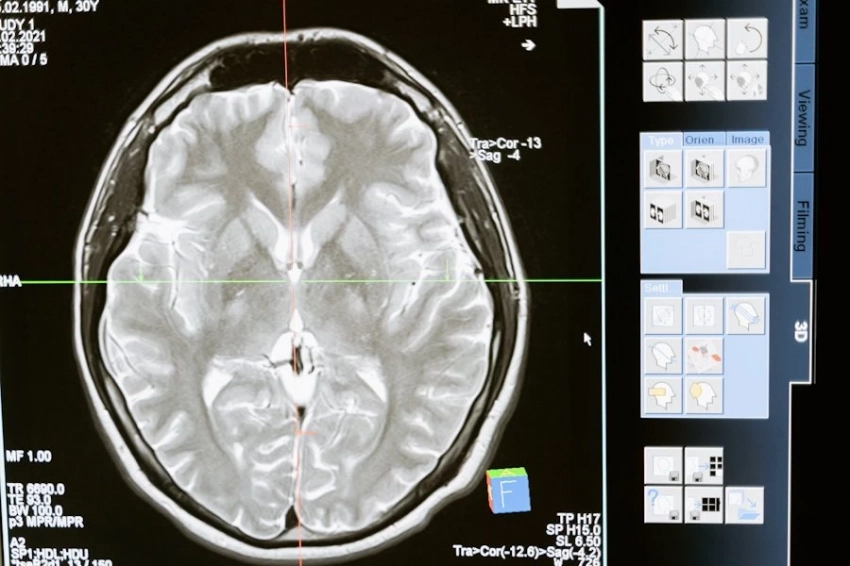

«Учитывая при подсчете баллов такие немодифицируемые факторы, как возраст, пол и образование, мы смогли сосредоточиться исключительно на риске развития деменции, связанном только с образом жизни участника», — сказал Пейс. «Затем мы применили инструменты сканирования мозга, такие как магнитно-резонансная томография (МРТ) для изучения структуры мозга, электроэнцефалографию (ЭЭГ) для определения электрической активности мозга и ряд когнитивных тестов для оценки памяти и мыслительных способностей».